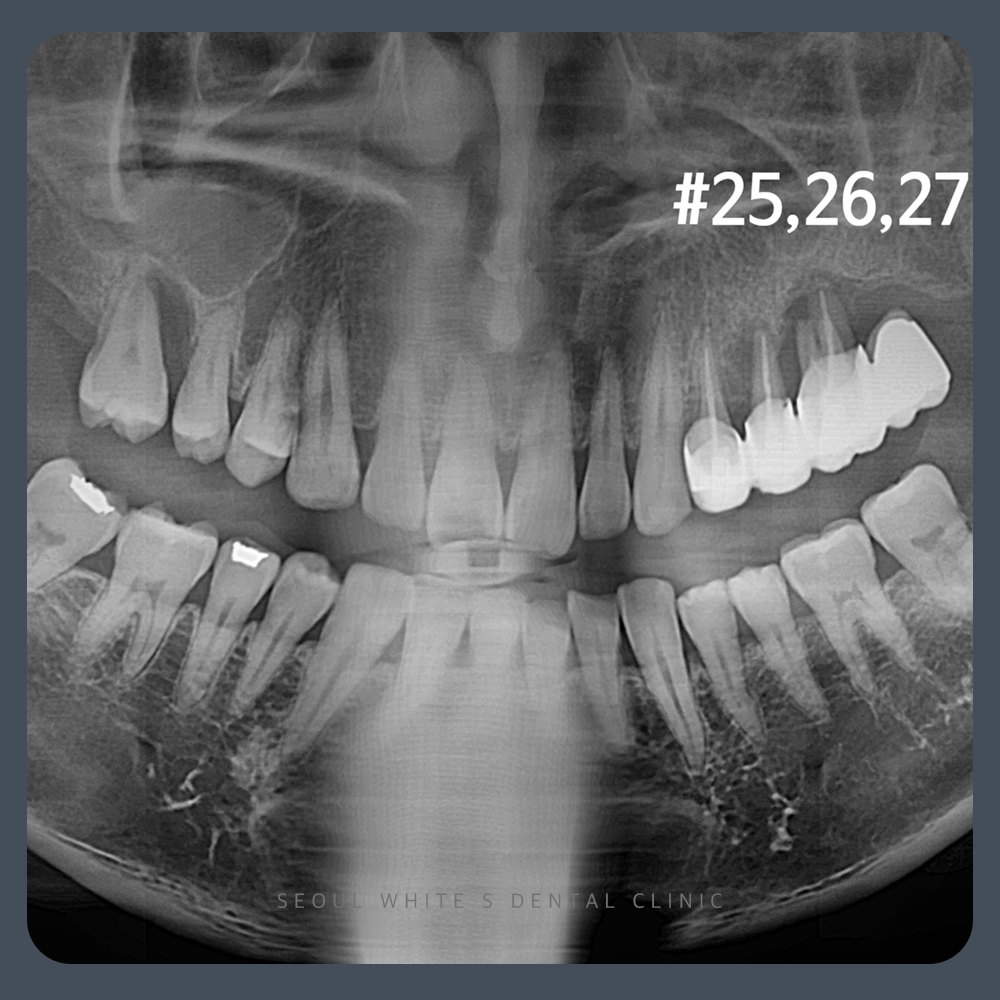

기존 브릿지를 모두 제거할 것인지, 상악동 거상술 시 어떤 접근 방법을 택할 것인지, 정밀 검진 결과, 브릿지 주변 치아 상태를 확인했을 때 #25, 26, 27번 치아는 발치가 필요하다고 판단되었습니다. 다만 소구치 1개(#24)는 보존 가능하여 자연치를 유지하면서 기능을 회복시키는 방향으로 치료 계획을 수립했습니다.

또한 상악동 거상술을 고려하여 뼈의 잔존 두께를 측정한 결과, 5mm 이상으로 확인되었습니다. 이는 환자분이 증상을 방치하지 않고 적절한 시기에 내원해주신 덕분에 뼈가 충분히 보존된 모습을 볼 수 있습니다. 따라서 불필요하게 측방접근법을 사용할 필요 없이, 현재 조건에서 충분히 가능한 상방접근법을 적용하여 수술을 진행할 수 있었습니다.